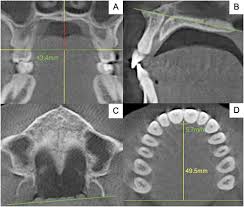

2 months ago i went to this ortho and he told me that i dont need an palate expander and when i went Yesterday he told me im gonna have to get one

Is it possible that he just tries to make more money or sum?